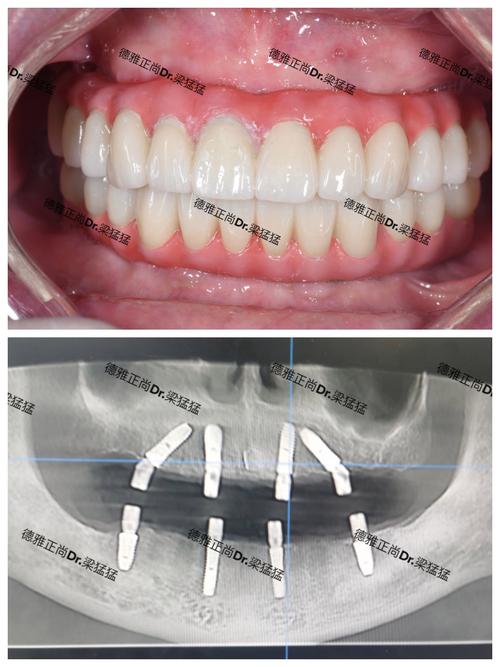

种植修复前的正畸考量是种植成功的关键,种植体需要足够的骨组织支持和健康的牙周环境,部分患者因牙齿缺失导致邻牙倾斜、对颌牙伸长,需通过正畸治疗调整牙齿位置,为种植创造理想条件,通过关闭缺牙间隙、纠正伸长牙、调整咬合平面,确保种植体植入位置符合生物力学要求,避免种植后咬合创伤,对于骨量不足的患者,正畸还可结合骨增量技术(如引导骨再生、牵成成骨),通过牙齿移动引导牙槽骨改建,提升种植区域骨量,提高种植成功率,种植前正畸需综合考虑患者年龄、缺牙时间、牙周状况等因素,制定个性化方案,通常需6-18个月完成。

正畸与种植联合治疗的优势在于实现功能与美学的统一,正畸可为种植修复奠定基础,解决牙齿排列问题;种植则能修复缺失牙,恢复咀嚼功能;牙周治疗贯穿全程,保障治疗安全,对于牙周病伴牙列缺损、错颌畸形的患者,先通过牙周治疗控制炎症,再通过正畸调整牙齿位置,最后实施种植修复,可显著提升治疗效果,减少并发症,远期效果更稳定,多学科协作能充分发挥各专科优势,为患者提供从预防、治疗到维护的全方位口腔健康管理。

正畸与种植联合治疗中的牙周管理要点 | 治疗阶段 | 牙周处理重点 | 正畸目标 | 种植注意事项 | |----------------|---------------------------------------|-----------------------------------|-----------------------------------| | 治疗前准备 | 牙周基础治疗,控制炎症,评估骨量 | 排列牙齿,调整咬合,开辟种植间隙 | 确定种植位点,评估骨密度 | | 正畸治疗中 | 定期牙周维护,预防牙龈退缩,控制菌斑 | 精细移动牙齿,避免牙根吸收 | 暂缓种植,待正畸结束后评估骨量 | | 种植修复期 | 种植体周围炎预防,维护种植体健康 | 调整咬合,确保种植体受力均匀 | 选择合适种植体,避免咬合干扰 | | 种植后维护 | 定期复查种植体周围,洁治刮治 | 保持正畸效果,防止复发 | 避免咬硬物,注意口腔卫生 |